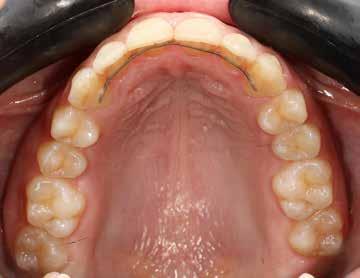

Minden fogszabályozó kezelés után nagyon fontos a retenció, de ilyen eltérés esetén különösen, mivel a recidíva veszély nyitott harapás esetén a legnagyobb. A fogak és a harapás megtartása fix és kivehető retainer-ekkel történik.

A kivehető helyben-tartók legfontosabb eleme a mindkét fogívet összekötő ún. Splint (19. kép), amely egyrészt saggitálisan tartja a helyén a mandibulát, hogy ne csússzon vissza hátrafelé, másrészt segít a harapás zártan tartásában a növekedés teljes befejeződéséig.